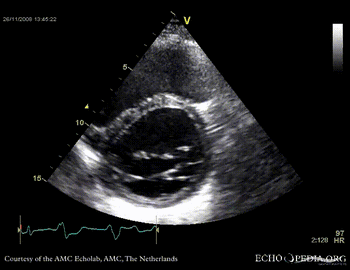

Dilated cardiomyopathy with severe mitral valve regurgitation

Courtesy of: J. Vleugels, AMC, The Netherlands